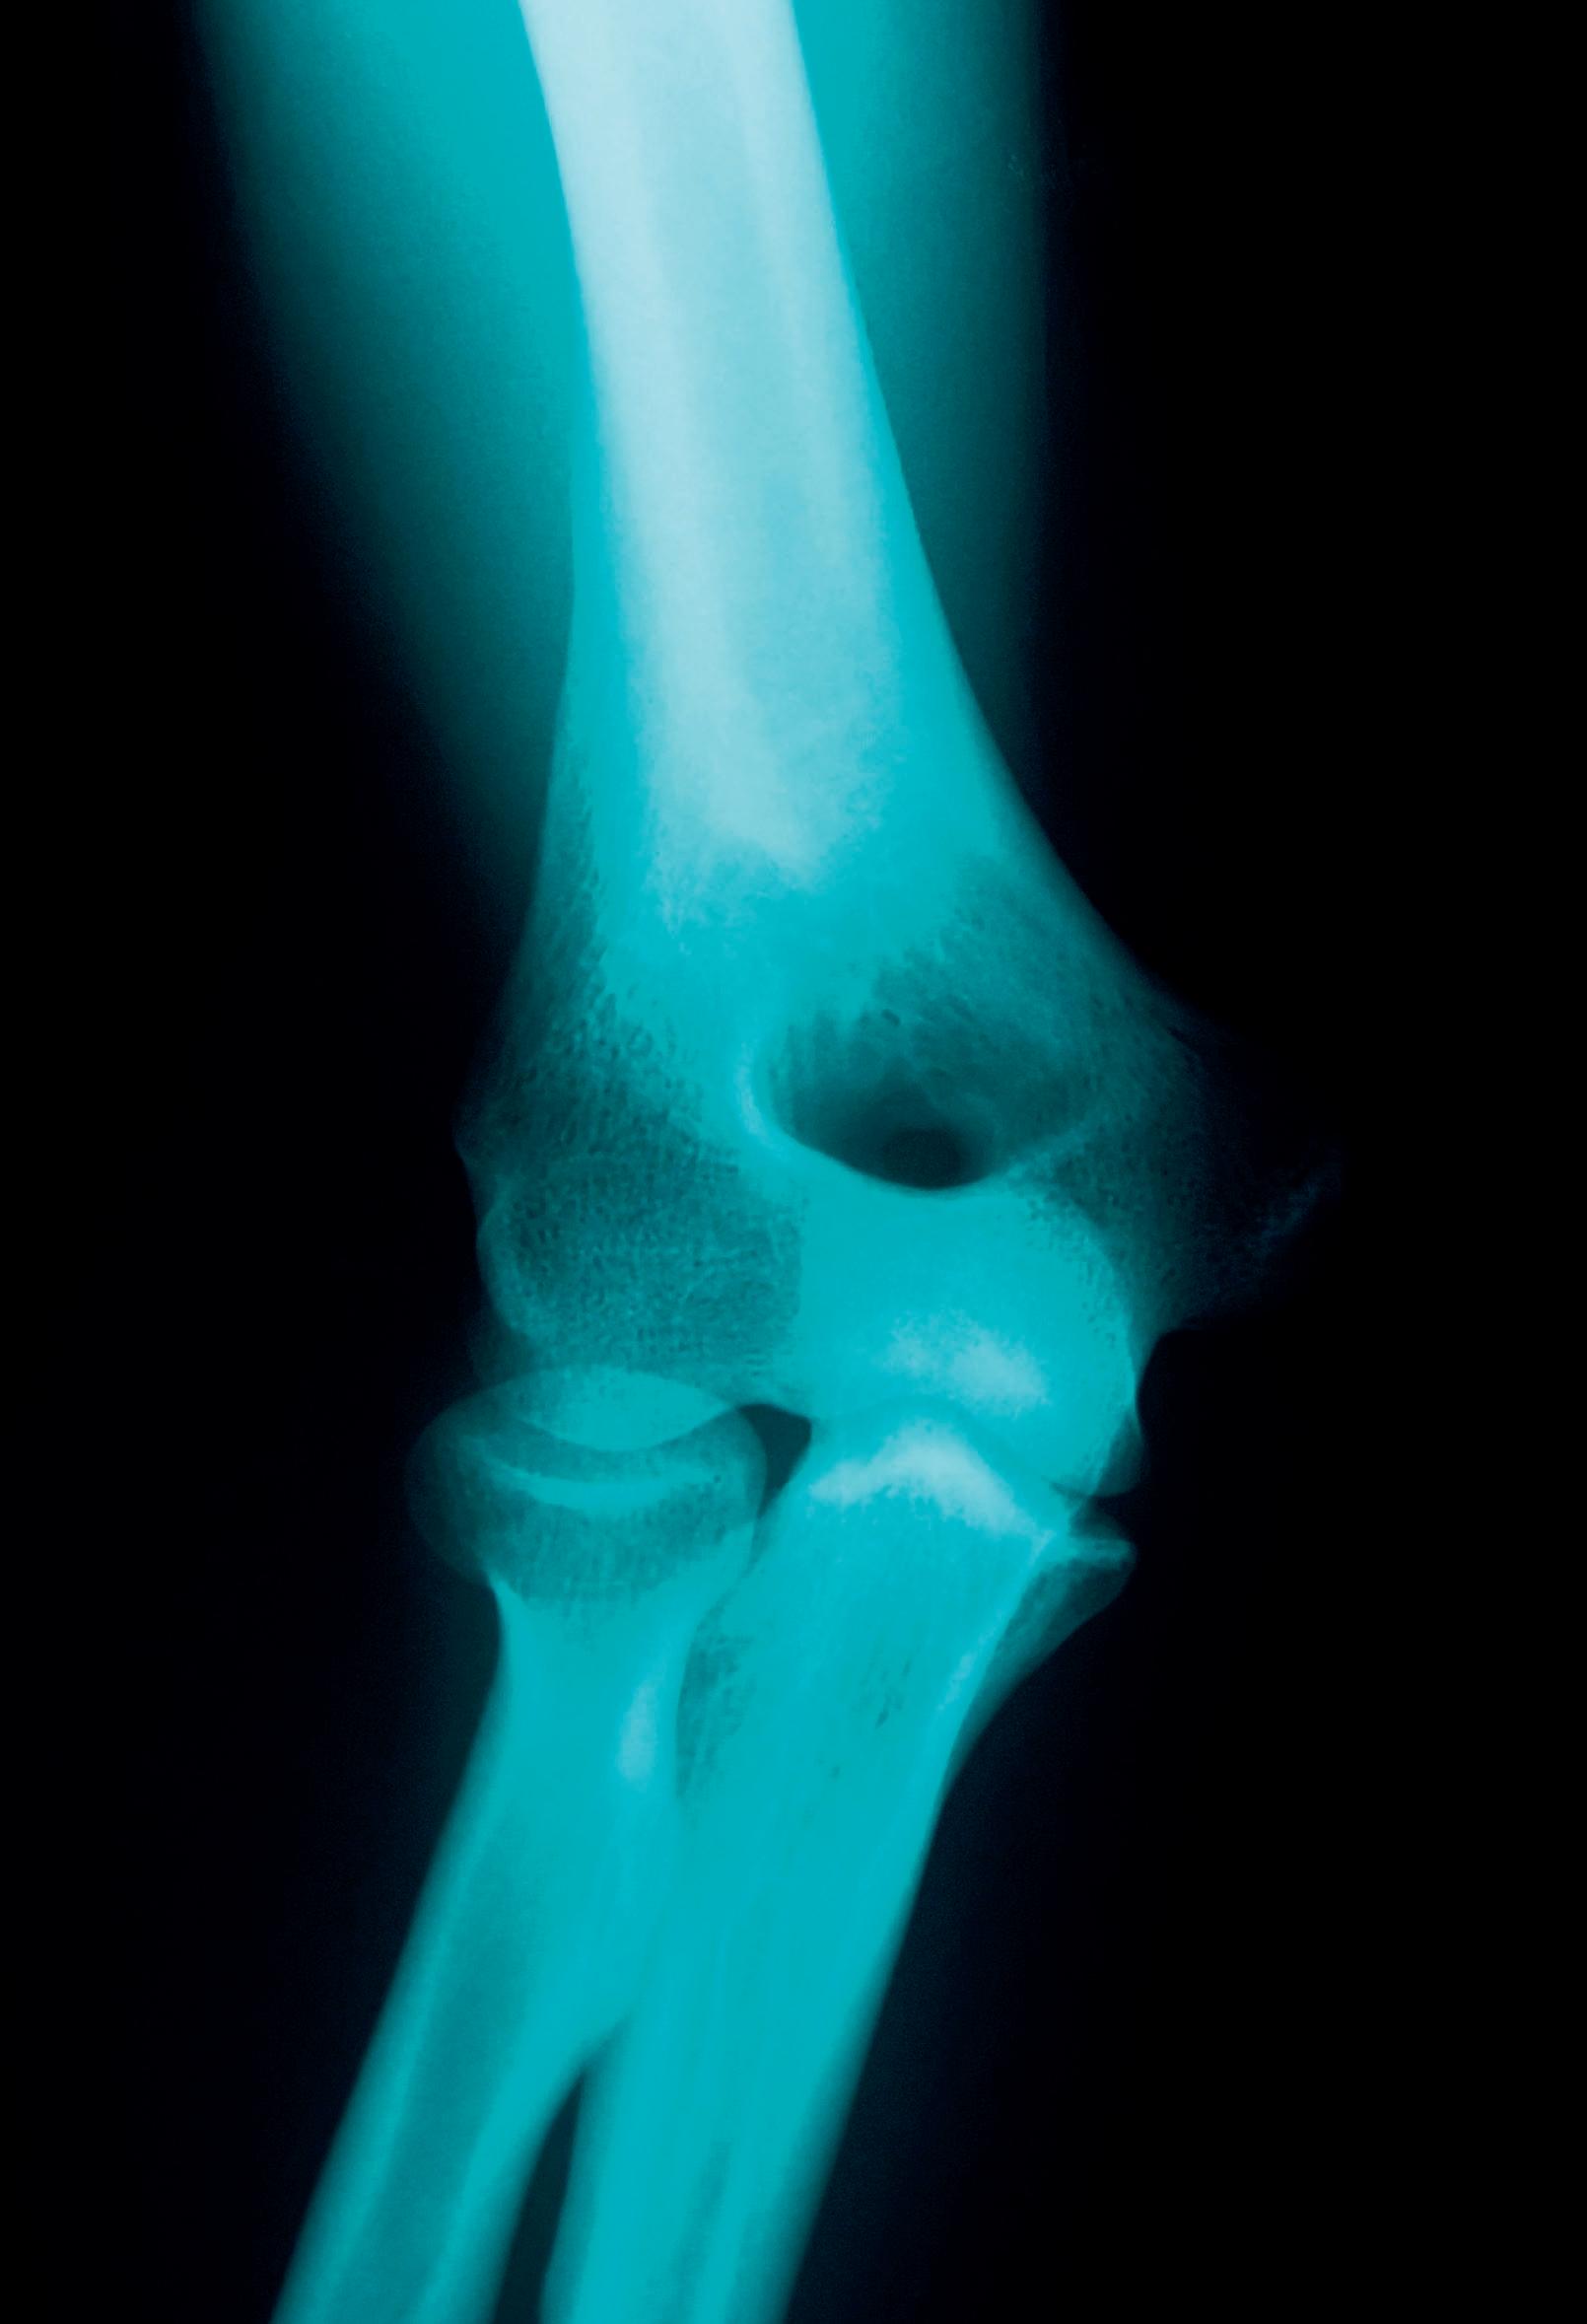

34 | Hellenic Medical Review ΣΥΝΕΝΤΕΥΞΗ Γεώργιος Λυρίτης: Η οστεοπόρωση προκαλεί στη χώρα μας καθημερινά 11 κατάγματα ανά ώρα ΣΥΝ Ε ΝΤΕΥΞΗ ΣΤΗ Ν Ε ΛΛΗ ΚΑΨ Η

Η οστεοπόρωση είναι μια σιωπηλή νόσος, η οποία όμως αριθμεί περίπου 700.000 πάσχοντες στη χώρα μαaς, εκ των οποίων σχεδόν το 80% ήταν

γυναίκες, τονίζει ο Γεώργιος Λυρίτης, Ομότιμος Καθηγητής Ορθοπαιδικής

ΕΚΠΑ, Πρόεδρος του Ελληνικού Ιδρύματος Οστεοπόρωσης (ΕΛΙΟΣ), μιλώντας

στο Hellenic Medical Review. Και προσθέτει ότι οι κοινωνικοοικονομικές

επιπτώσεις της οστεοπόρωσης είναι σημαντικές και η αντιμετώπισή της

αποτελεί βαρύ οικονομικό φορτίο για τα συστήματα υγείας αλλά και ψυχολογικό

τόσο για τους ίδιους τους ασθενείς όσο και το περιβάλλον τους.

Ποια είναι τα συμπτώματα και οι κλινικές εκδηλώσεις της οστεοπόρωσης

και ποια η επίπτωσή τους στην υγεία

και στην ποιότητα ζωής των ασθενών; Ποια είναι τα διαγνωστικά προβλήματα; Η οστεοπόρωση είναι μια σιωπηλή

νόσος χωρίς συμπτώματα μέχρι να συμβεί το πρώτο κάταγμα μετά από ελαφρύ

ή καθόλου τραυματισμό. Τα συχνότερα

οστεοπορωτικά κατάγματα συμβαίνουν

πέρα από το ισχίο και στη σπονδυλική

στήλη τα οποία μπορεί να προκαλούν

πόνο κατά τις καθημερινές δραστηριότητες, σοβαρή αναπηρία, απώλεια ύψους και

κύφωση με αποτέλεσμα να υποβαθμίζεται

δραστικά η ποιότητα ζωής των ασθενών.

Εκτός από τα κατάγματα, η κύφωση είναι ένα πρόβλημα που μπορεί να επιδράσει

αρνητικά στη λειτουργία των πνευμόνων

και της καρδιάς.

Οι κοινωνικοοικονομικές επιπτώσεις της οστεοπόρωσης είναι σημαντικές και η αντιμετώπισή της αποτελεί βαρύ οικονομικό φορτίο για τα συστήματα υγείας αλλά και ψυχολογικό τόσο για τους ίδιους τους ασθενείς όσο και το περιβάλλον τους. Όπως ήδη ανέφερα τα κατάγματα του αξονικού σκελετού είναι ιδιαίτερα δύσκολο να διαγνωστούν εφόσον δεν συνοδεύονται από τραυματισμό.